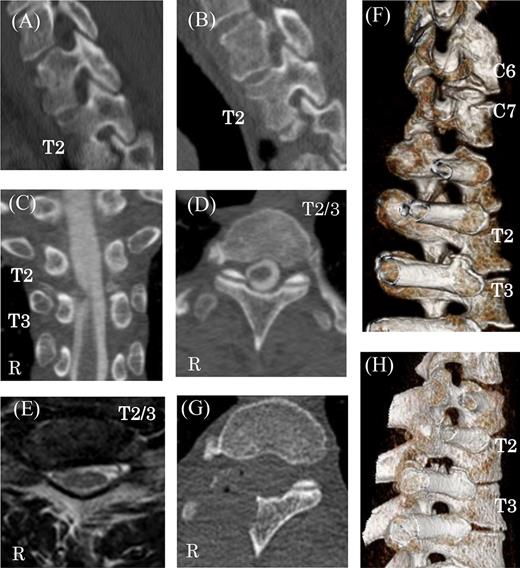

Preoperative and postoperative CT and MR images. (A) Thoracic sagittal views of CT image before cervical anterior fusion at right T2 nerve root canals. Preoperative multi-planar CT images (B–D) and reconstructed 3D images showing right C6–7 and T2–3 nerve root canal stenosis caused by bone spurs of facets and vertebral bodies (F and H). MR imaging of protruded disks at the T2–3 level (E). Postoperative CT shows the decompression of the right T2–3 thoracic nerve root canal (G).

The width and height of the nerve root canal on the right measured 6.4 mm and 4.2 mm at C7 and 5.2 mm and 5.1 mm at T2, respectively [1]. The right C7 and T2 nerve root canals were narrow compared to left side (left C7 width 8.0 mm, height 8.2 mm; left T2 width 9.9 mm, height 10.5 mm). From C5−T4, mean width was 9.4 ± 1.8 mm and mean height was 9.2 ± 2.4 mm. Before anterior cervical fusion, the width and height of the nerve root canal on the right at T2 had been 7.4 mm and 5.0 mm and on the left had been 8.6 mm and 12.2 mm, respectively (Fig. 2A). These findings indicate that the nerve root canals on the right at C7 and T2 were degenerative.

A 60-year-old man presented with 3 months of progressive pain in the right axilla and posteromedial upper extremity. He had undergone C5–6 anterior fusion for cervical spondylosis 5 years prior (Fig. 1B). He had returned to his job as a taxi driver after the anterior fusion. He did not have any traumatic injury or traffic accidents after his anterior fusion. His numerical pain scale rating was 10/10. Examination revealed no sensory disturbance, no abnormal tendon-jerk reflexes and progression of muscle weakness. Cervicothoracic scoliosis had been diagnosed before his anterior cervical fusion (Fig. 1A). Roentgenograms showed scoliosis with a right cervicothoracic curvature with a Cobb angle of 17 degrees before his anterior fusion (Fig. 1A) and 19 degrees on referral to our hospital (Fig. 1B). In addition, computed tomography (CT) scanning revealed bone spurs of the C6–7 facets (Fig. 2F). Magnetic resonance (MR) imaging showed a decrease in intervertebral height, but the nerve root canal was preserved at the C6–7 level. CT images also showed osteophytes of the superior costal facet and articular process at the T2–3 level (Fig. 2B–D). MR images demonstrated a protruded disc at the T2–3 level (Fig. 2E and F).